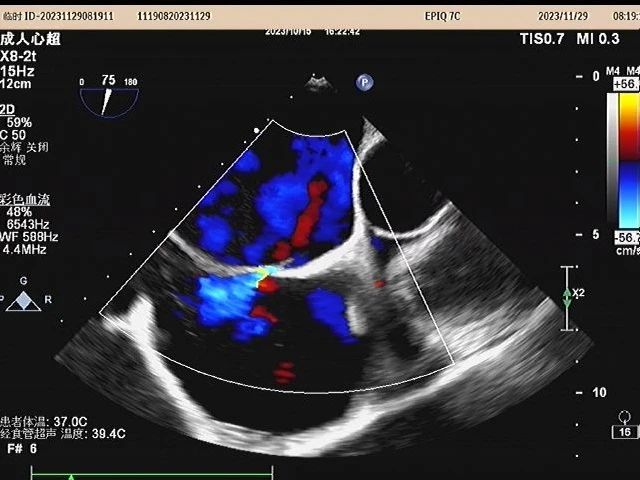

近日,英德市人民医院神经内科一区收治1名41岁女性患者(化名:张女士)。医生在询问病史得知,张女士2月前出现右侧肢体麻木乏力症状,且症状反复发作,多次外院就医,效果不佳。门诊医生详细询问张女士的身体状况,怀疑其是隐匿性卒中患者,需住院治疗。神经内科开展主任查房和全科讨论,认为隐匿性卒中病因考虑为心源性,为进一步明确病因,建议尽快完善“经食道超声心动图检查或者发泡试验”。在神经内科与超声科通力合作,对张女士进行了经食道超声心动图检查。超声检查提示:卵圆孔未闭。明确了隐匿性卒中的病因,为下一步实施精准治疗提供了有力依据。

经食道超声心动图检查是将超声探头置入食管内,从心脏的后方向前近距离探查心脏深部结构的一种检测方法。这种方法避免了胸壁、肺气肥胖等因素的干扰,可显示出更为清晰的图像,提高了心血管疾病的诊断可靠性,更便于心脏手术中的超声监测与评价。

1.由于经食道超声彩色多普勒从心脏后方扫描检查,不受胸壁结构和肺内气体的干扰,可以获得普通超声难以得到的切面和图像质量,适合肥胖、肺气肿、胸廓畸形或近期胸部手术后的患者。